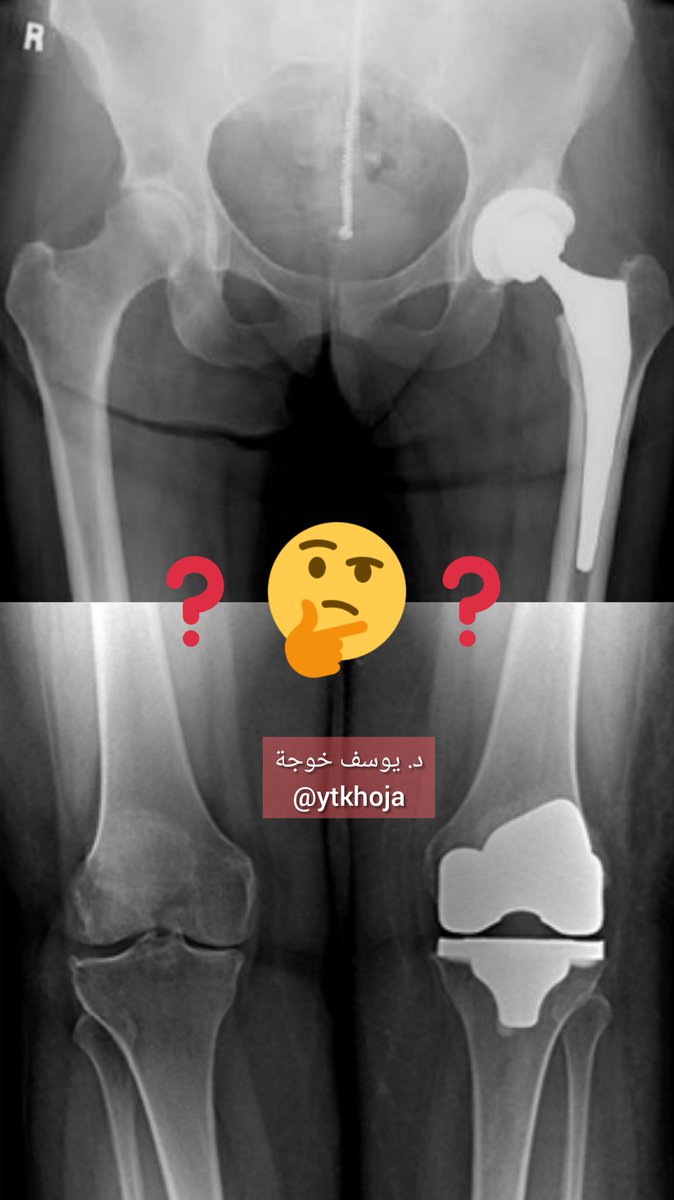

قرار توقيت إجراء عملية #استبدال_المفصل بمفصل صناعي لعلاج #خشونة و #احتكاك الورك أو الركبة قرار صعب على المريض والجراح 😓

عوامل وعلامات تؤيد بأن المريض بحاجة لعملية #استبدال_المفصل للركبة أو الورك:

نفضل تأخير العملية خصوصاً لمن أعمارهم تقل عن ٦٠ سنة لأن المفصل الصناعي له عمر افتراضي وبعدها قد نحتاج لاستبداله مرة أخرى إذا دعت الحاجة لكن هذا لا يعني عدم إجرائها إطلاقاً لمن كان عمره أقل من ٦٠ سنة حسب الحالة والعوامل.